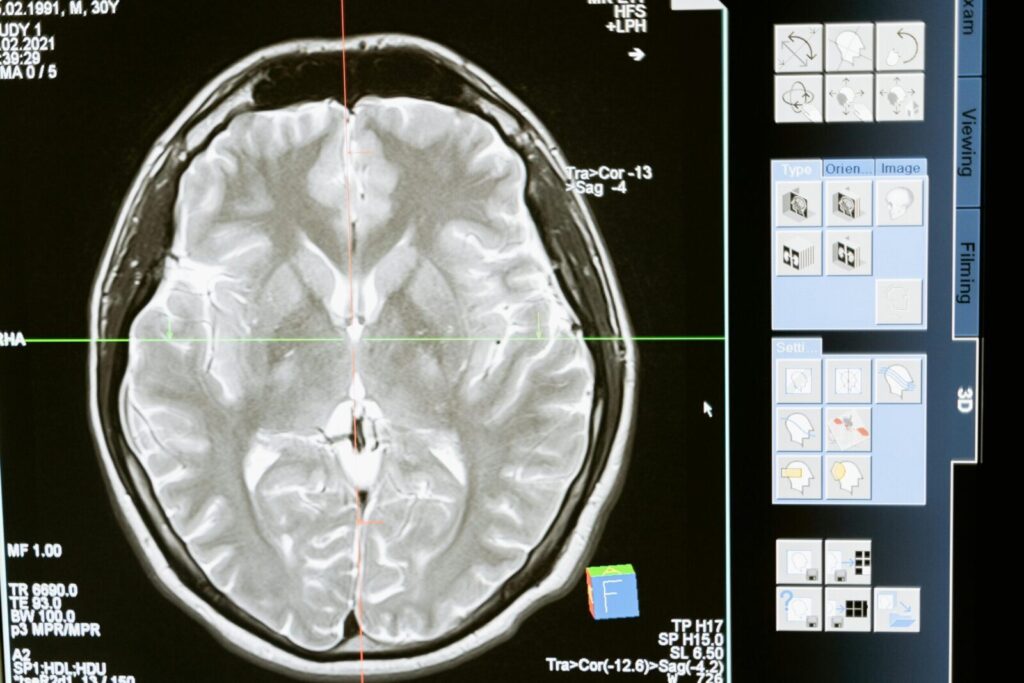

Intricate MRI brain scan displayed on a computer screen for medical analysis and diagnosis.

Pastaraisiais metais ME/CFS vis dažniau vertinamas kaip biologinė liga, nors vieno visuotinai priimto diagnostinio testo iki šiol nėra. Mokslinėje literatūroje aptariami objektyvūs pokyčiai, susiję su nervų sistema ir organizmo atsako į krūvį sutrikimais, tačiau klinikinėje praktikoje pacientų kelias iki diagnozės neretai išlieka ilgas.